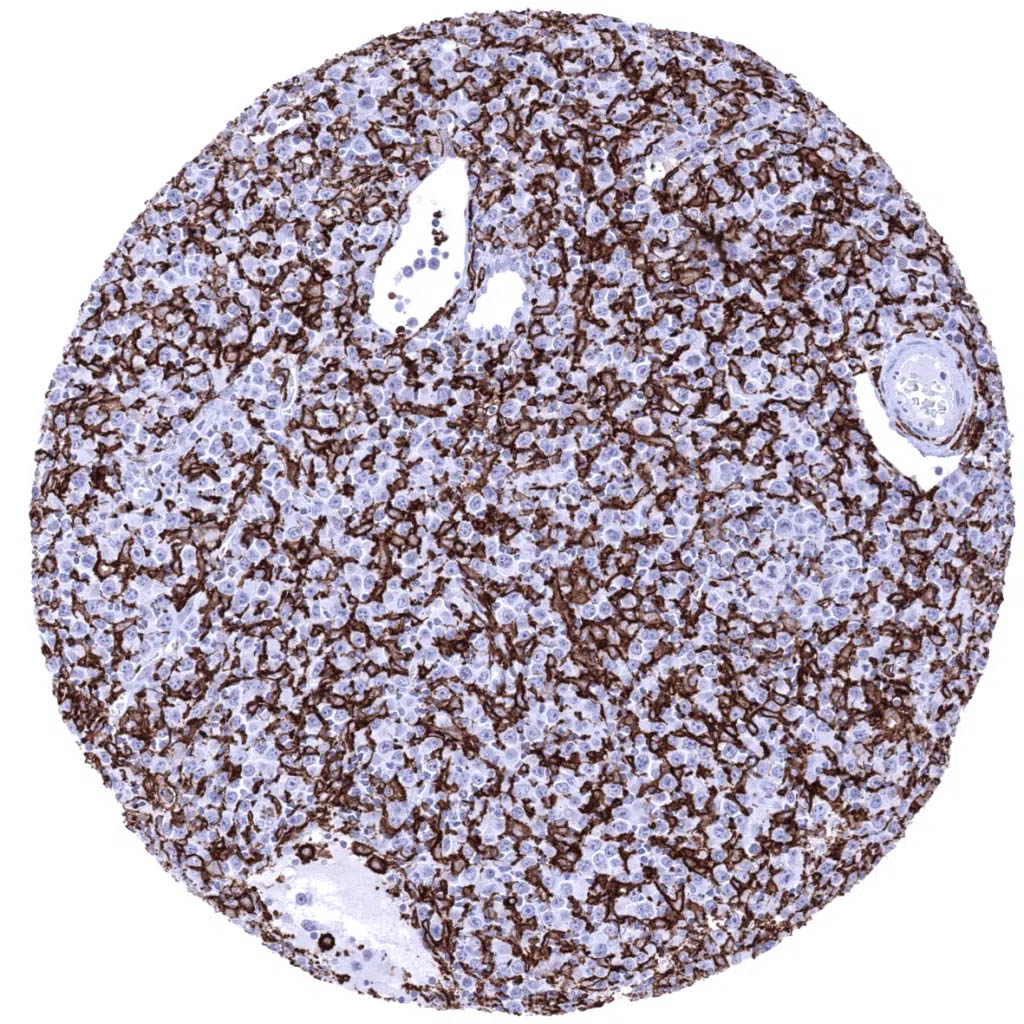

Iba1 antibody [MSVA-955M] HistoMAX

Lymph node - Hodgkin’s lymphoma almost completely consisting of AIF1 positive inflammatory cells. Note: Hodgkin’s and Reed Sternberg cells are AIF1 negative.